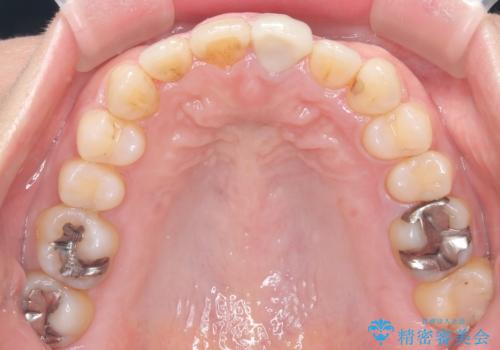

治療中は咬合バランスや歯列の中心(正中)の位置にも注意を払い、最終的には上下の正中が一致し、左右の臼歯関係も理想的な形に改善されました。見た目の変化はもちろん、かみ合わせの安定や清掃のしやすさも向上。

患者さんからは「笑ったときの印象が大きく変わって嬉しい」「しっかり噛めるようになった」との感想をいただきました。現在は保定装置で後戻りを防ぎながら、良好な状態を維持しています。